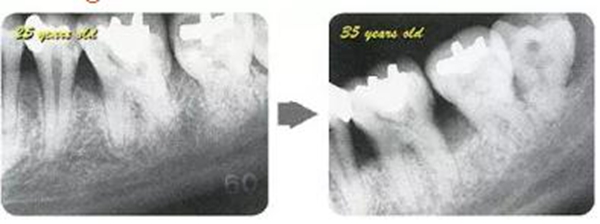

牙周病的發(fā)展因部位不同而發(fā)展程度不同的。10點(diǎn)后的狀態(tài)參考病例①和參考病例②的磨牙處的狀態(tài)相比較,思考下沒(méi)接受治療病情發(fā)展的特別性吧。

參考病例① 35歲女性

在左下第一磨牙在25歲時(shí)近中處可以看到垂直性的骨吸收,但35歲時(shí)吸收停止,原本沒(méi)有見(jiàn)到的遠(yuǎn)中處骨吸收的,現(xiàn)在卻吸收得很嚴(yán)重。

在右下處,原本有大量骨吸收的第一磨牙處的吸收卻變緩慢,原本沒(méi)有吸收的第二前磨牙卻出現(xiàn)了吸收。出現(xiàn)吸收的左上第一磨牙的遠(yuǎn)中處,吸收得越來(lái)越多了。

把10年間的變化做成表格。牙周病的發(fā)展根據(jù)各個(gè)人會(huì)不同,即使通一個(gè)人,不同牙齒,不同牙面發(fā)展的狀態(tài)也不同。